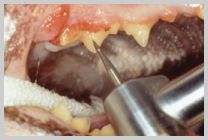

Roto pro burs - flame

and perio

Rotosonic scalers remove calculus from the

tooth by both high-speed rotation and ultrasonic

vibration.

They use eight sided friction grip (FG) burs inserted into the

high-speed handpiece of an air driven dental unit.

They come in two shapes - flame and perio. They are no longer in

common general use in veterinary dental practice as they are prone

to cause damage to the enamel, dentine and gingival tissues, unless

they are used with great care. Light pressure is required, as is

copious irrigation, to prevent severe enamel damage.